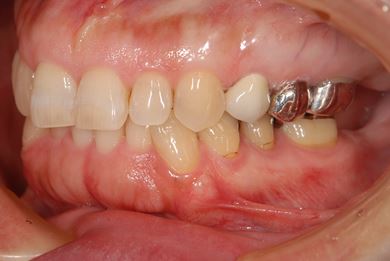

治療前

• 治療前

治療後

• 治療後